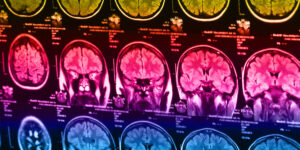

Plastics and autism: Study highlights BPA’s potential impact on boys’ brain development

A recent study suggests that prenatal exposure to BPA may increase autism risk in boys with low aromatase enzyme activity, possibly through estrogen-related brain changes. However, it does not confirm BPA as a direct cause of autism.